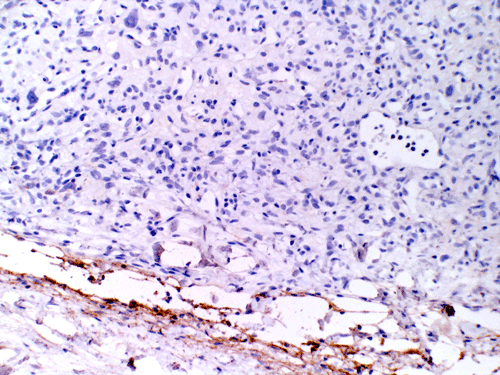

The mass consists of a mixture of spindle cells and clear cells. There is a rich vascular network (Panel A) with sinsusoidal dilatation but no anastomosis of the vascular channels. The endothelial cells appear lean and not protruding into the vascular channel. The clear cells appear to have foamy cytoplasm (̃ in Panel B). The nuclei are hyperchromatic and may appear slighly grooved or lobuated. On immunohistochemistry, the foamy cells are strongly reactive for inhibin (Panel C). These cells are also reactive for S100 protein (Panel D) and neural specific enolase (Panel E) . No immunoreactivity for epithelial membrane antigen (EMA) is observed (Panel F). The tumor is not immunoreactive for cytokeratin.

The truely helpful immunohistochemical marker in this case is inhibin. S100 protein, neural specific enolase, and EMA are rather non-specific.

Microscopically, hemangioblastomas consist of foamy to clear stromal cells interspersed with endothelium lined vascular channels. Clear vacuoles within the stromal cells can be stained with Oil red-O or similar stain if applied to frozen sections. The stromal cells stain strongly for epidermal growth factor receptor (EGFR) and platelet-derived growth receptor factor alpha (PDGF-alpha) 12 and inhibin 13. The stromal cells are typically negative for epithelial membrane antigen (EMA) and cytokeratin 14. In a small number of cases, the stromal cells express glial fibrillary acidic protein (GFAP) 7, 14 and S100 protein 14. These staining results should be interpreted with case as they may represent entrapped glial cells. The admixed capillaries will stain for with typical endothelial markers (Factor-VIII and others) 15, but the stromal cells are typically negative for the endothelial markers. To this date, the pathogenesis and cell origin of hemangioblastomas is not certain.

The primary entity that must be ruled out is metastatic renal cell carcinoma as it can have a similar histologic appearance on H&E and has a similar incidence in patients with von Hippel-Lindau syndrome as that of hemangioblastoma. On hematoxylin-eosin stained sections, renal cell carcinoma can have necrosis, mitosis and large nucleoli, features almost always absent on hemangioblastoma. However, it must also be noted that metastatic renal cell carcinoma can appear rather bland and with out significant atypia. Renal cell carcinoma is also immunoreactive for cytokeratin, CD10, and EMA, while hemangioblastoma is positive for inhibin 13, but negative for cytokeratin, CD10, and EMA.